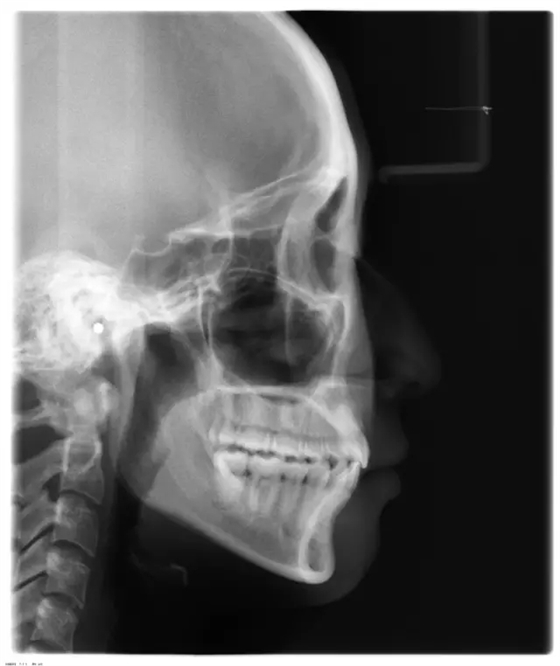

患者側(cè)面凸,鼻唇角較銳,笑時(shí)露齦笑明顯上下牙列擁擠,磨牙尖牙Ⅱ 類關(guān)系,3 度的深覆牙合,上頜中切牙伸長內(nèi)傾拔除上頜雙側(cè)的第一前磨牙,先粘上頜高轉(zhuǎn)矩的自鎖托槽排齊牙列,唇向開展上頜切牙,有一定的覆蓋,粘下頜標(biāo)準(zhǔn)轉(zhuǎn)矩托槽,上頜 1, 2 之間植入種植支抗壓入,同時(shí)后牙 5, 6 之間植入種植支抗內(nèi)收前牙,打開咬合關(guān)閉間隙。治療關(guān)鍵:前牙轉(zhuǎn)矩的控制第 1 個(gè)月 上頜粘上 Damon Q 高轉(zhuǎn)矩托槽,上 .014 熱激活 NiTi 絲。第 3 個(gè)月 上換 .014 x .025 熱激活 NiTi 絲。第 5 個(gè)月 上頜基本排齊,覆蓋增大,上換 .017 x .025 NiTi絲,下頜粘托槽,下 .014 熱激活 NiTi 絲。第 7 個(gè)月 上 .017 x .025 NiTi 絲加搖椅,下?lián)Q .014 x .025 熱激活 NiTi 絲第 9 個(gè)月 上頜換 .019 x .025 NiTi 絲加搖椅,下頜換 .017 x .025 NiTi 絲第 11 個(gè)月 下頜換 .019 x .025 加搖椅,上頜 1, 2 之間, 5, 6 之間植入種植釘,下頜出現(xiàn)散隙。第 13 個(gè)月 上頜換 .019 x .025ss 加搖椅,前牙種植釘用 Power Chain 壓低前牙(每側(cè) 100g),后牙種植釘關(guān)閉間隙(每側(cè) 150g),下?lián)Q .019 x .025ss,Power Chain 關(guān)閉間隙。第 19 個(gè)月 上頜前牙基本壓低到位去除前牙種植釘,繼續(xù)用關(guān)閉間隙,下頜散隙關(guān)閉。

第 22 個(gè)月 上頜覆蓋變小,去除 5, 6 之間種植釘,后牙前移關(guān)閉間隙。第 30 個(gè)月 患者未配合中線牽引,下中線仍有 1mm 右偏,患者對矯治效果滿意要求拆除,拆除固定矯治器,取模制作壓模保持器。 1.骨性 Ⅱ 類的患者內(nèi)收前牙時(shí)需對上頜前牙的轉(zhuǎn)矩進(jìn)行較好的控制才能獲得良好的面型和唇部形態(tài)。 2.露齦笑的患者治療前要分析其病因是唇、牙齦、牙齒、牙槽骨、上頜骨或多種因素結(jié)合,再制定矯治方案。 3.Ⅱ 類第二分類伴露齦笑的患者的上頜前牙移動軌跡是唇向開展-壓低-整體內(nèi)收。 4.Ⅱ 類第二分類牙齒舌傾比較厲害的情況,上頜中切牙慎用樹脂咬合墊。 5.壓低前牙或控根移動時(shí)容易發(fā)生牙根的吸收,需輕力緩慢的移動。